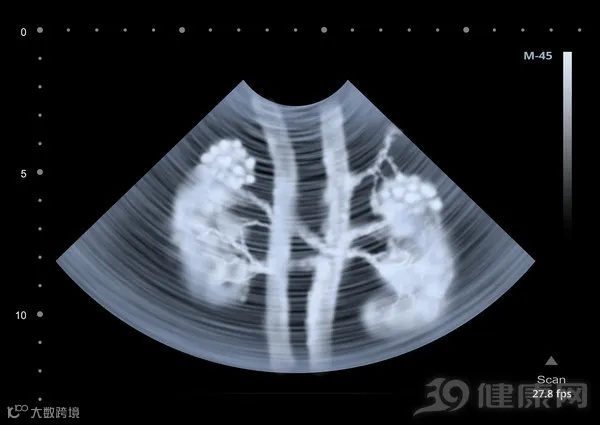

结石诊断方式二:B超

一种经济实惠检测结石的常规项目,使用超声仪器可以清晰地看到结石的具体大小,肾脏是否有积水,输尿管有没有扩展,是急性发作者的首选检查手段,也是预防结石的绝招,每年体检别忘记做。